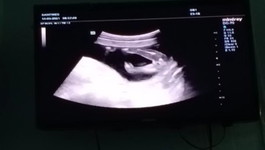

แบบนี้ชายหญิงคะ😂♥️

ลูกคนที่สองเเล้วตอนนี้น้องได้18wแล้วคะ หมอบอกว่าได้ผู้หญิงแต่เเอบกังวล ว่าจะเป็นผช

ถ้าดูจากภาพคือเห็นไม่ชัด แต่คุณหมอระบุเพศมาแล้วโอกาสพลาดน่าจะน้อยมากแล้วค่ะ

น่าจะ ผญ.นะคะ อ้าขนาดนี้ไม่มีไข่ ไม่มีจู๋